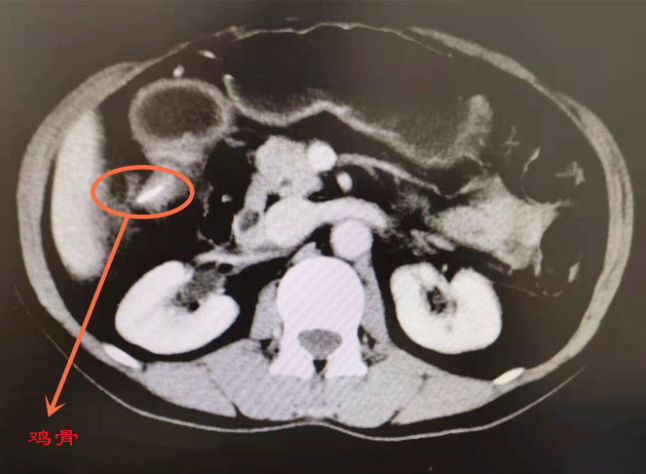

但自那以后,田女士的上腹总是会隐隐约约的疼痛,有时又是胀气。但她一直以为自己是“胃病”,还是没有太过在意。“越来越痛,呼吸用力了都会感觉痛。”因为腹部疼痛加剧,直到近期才去到了就近的医院。CT提示“十二指肠异物伴周围炎”可能性大,不过在尝试内镜检查后,发现该异物已经穿破十二指肠壁,并且主体部分已经进入腹腔,异物没能在内镜下被顺利取出。因为考虑到风险等问题,田女士暂未选择手术,只是进行了对症治疗。

但是,上腹疼痛的问题始终没有解决。而后,田女士来到了成都市第三人民医院问诊。经过内镜超声及腹部增强CT等更为细致的检查,普外科·肝胆胰外科团队发现其为“十二指肠球部区域异物伴肠穿孔,伴周围炎”。也就是说,这个惹祸的“鸡骨头”在体内顺着食道去到了胃里,又“一路颠簸”到十二指肠的位置。锋利的部位将肠道给扎穿后,暂时在此“安了家”。

经过术前讨论,普外科·肝胆胰团队决定利用腹腔镜微创技术为田女士展开治疗。“手术还是有一定的难度。”文君介绍说,术中发现扎穿十二指肠肠壁的条形异物,已经有约80%的部分突入进入腹腔,又被横结肠系膜、大网膜给“打包”,形成了一个炎性的肿块;剩下的尚有约20%的部分,嵌顿于十二指肠壁内。手术难点主要在于两点:一方面,十二指肠球部、降段与横结肠系膜、大网膜、横结肠的致密粘连导致解剖结构不清,在分离粘连的过程中,容易造成十二指肠、横结肠肠管损伤,术后容易发生肠瘘;另一方面,要完整取出异物,还需要解剖并打开异物穿孔处的十二指肠壁,术后容易发生十二指肠的狭窄或者肠瘘,而十二指肠液含有大量腐蚀性极强的胆汁及胰液等消化液,一旦发生肠瘘,可能造成腹腔内严重感染、出血等极为严重的后果。

经过复杂而精细的腹腔镜微创手术,普外科·肝胆胰外科文君医生团队在充分保护周围脏器的情况下,仔细分离并切除了异物所致的腹腔炎性包块;又在切开异物穿孔处的十二指肠壁后,将长度约4cm的鸡骨头完整取出,同时对十二指肠切口进行了仔细缝合修补。